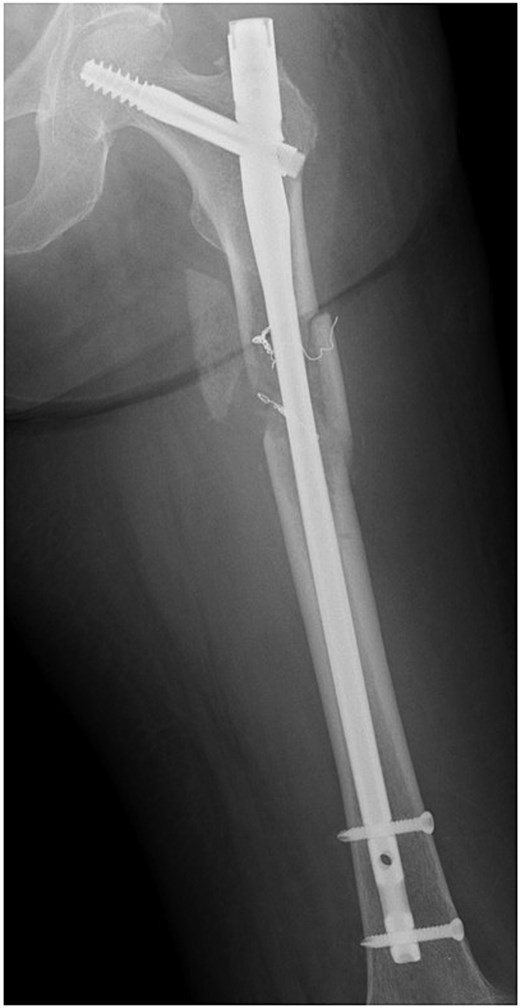

She was transferred to the catheterization laboratory, where coronary and lower extremity angiography revealed 90% stenosis of the left anterior descending artery and tumour blood supply via branches of the deep femoral artery (Figs 2a and 3a).

Coronary angiography findings. (a) Pre-treatment angiography showing 90% stenosis of the left anterior descending artery. (b) Post-treatment angiography showing improved blood flow in the left anterior descending artery after percutaneous coronary intervention.

Dual antiplatelet therapy (DAPT) with aspirin and prasugrel was initiated, followed by PCI with drug-eluting stents (DES) from the left main coronary trunk into the anterior descending artery (Fig. 3b).